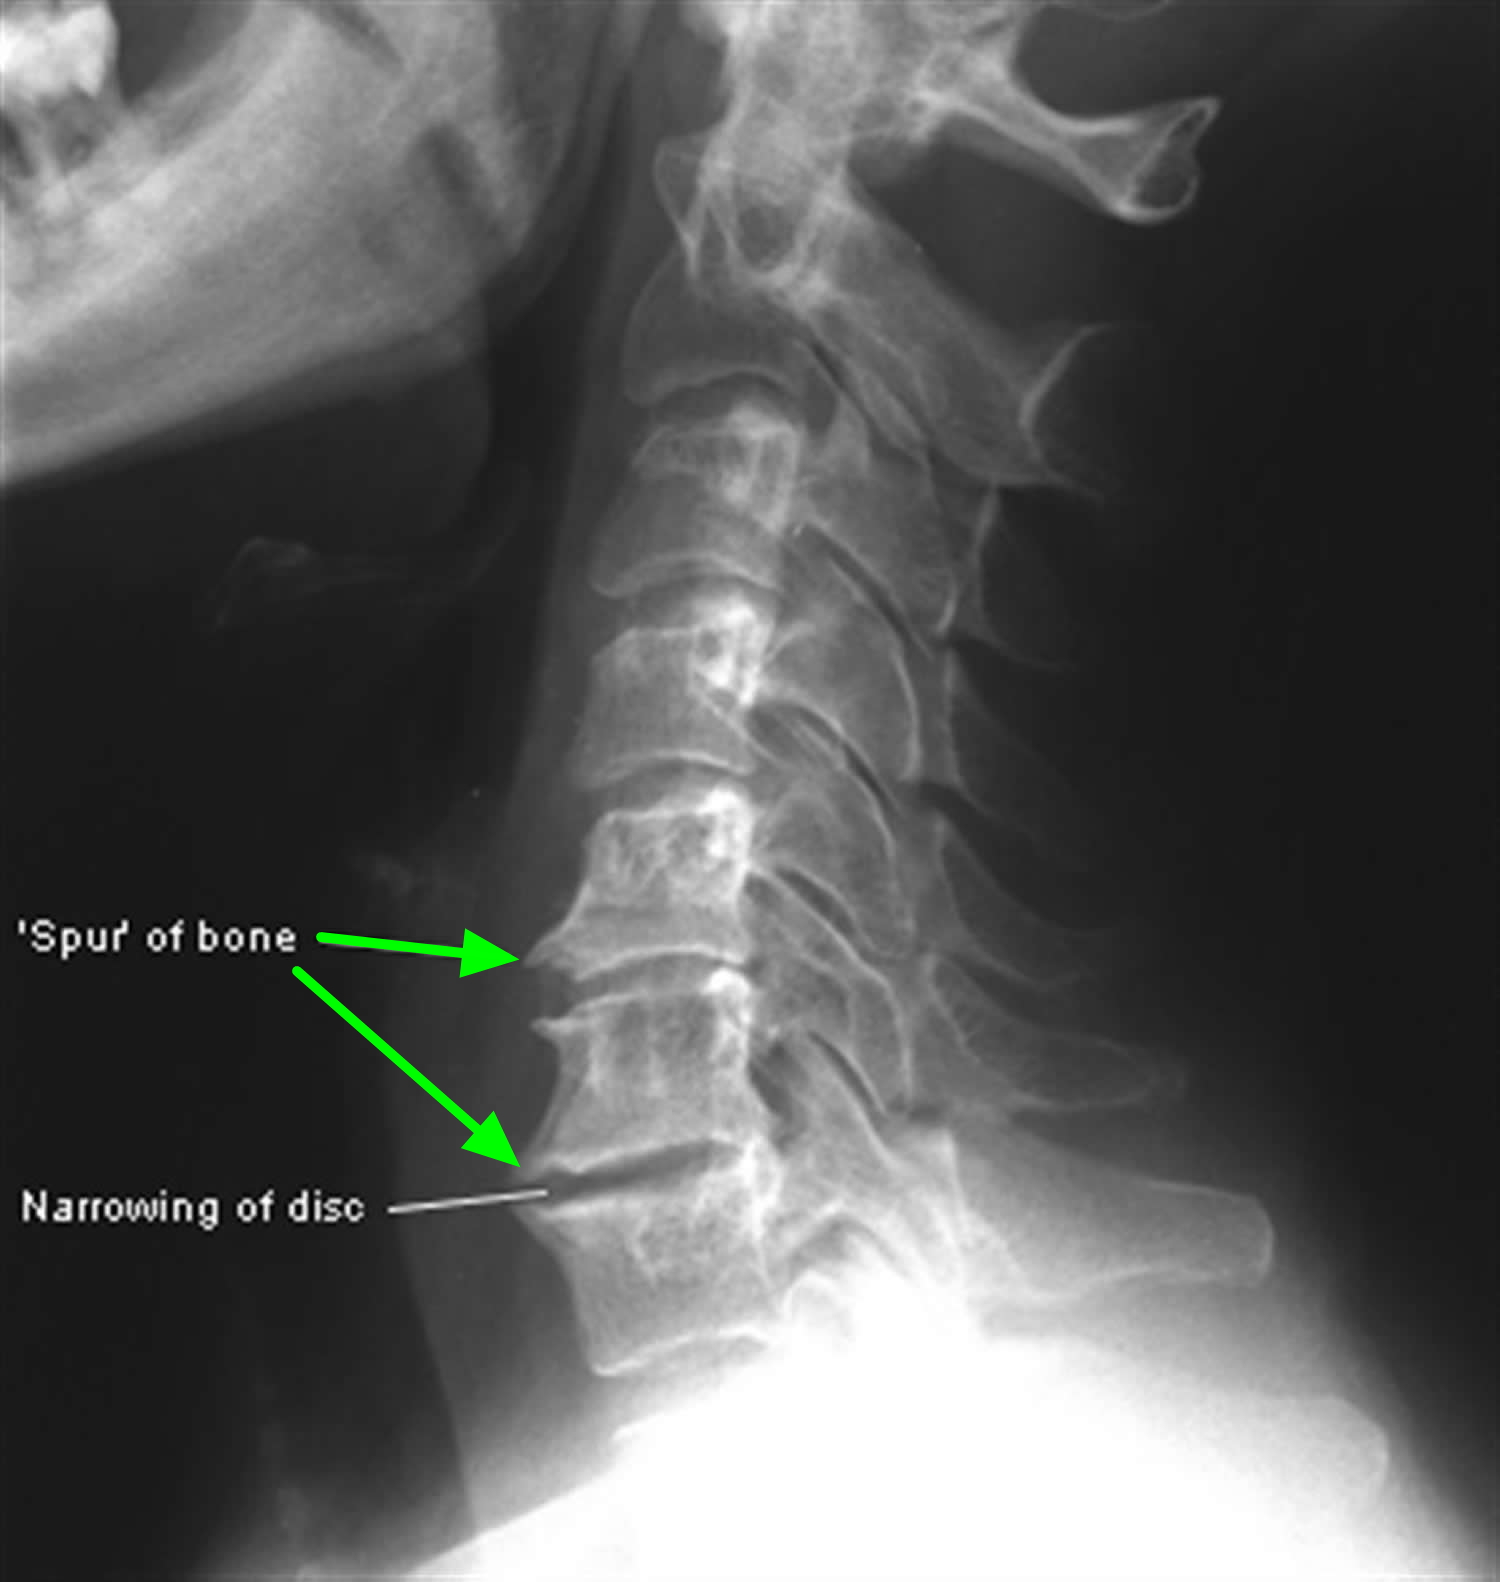

Waking up with a stiff neck is something most of us experience occasionally, but when that pain becomes a chronic companion, it may be a sign of deeper structural changes in your spine. One of the most common culprits for persistent neck discomfort and radiating pain is the development of bone spurs in neck regions, medically referred to as cervical osteophytes. These bony projections, which grow along the edges of the bones in your spine, are often the body's attempt to stabilize the area following age-related wear and tear. While they are not always painful, they can cause significant distress if they press against nerves or the spinal cord, leading to a condition known as cervical spondylosis.

Bone spurs in neck areas are essentially smooth, hard bumps of extra bone that form on the vertebrae. They are not “spurs” in the sharp, pointy sense; rather, they are rounded growths that develop in response to friction and pressure. As we age, the cushions between our vertebrae—the intervertebral discs—begin to dehydrate and shrink. This reduces the space between the bones and creates instability.

To compensate for this instability, the body naturally attempts to stabilize the spine by increasing the surface area of the vertebrae. It lays down additional bone, which eventually turns into these spurs. While the intent is to protect the spine, the result is often the opposite: the spurs can narrow the space available for nerves to exit the spinal canal, leading to compression, inflammation, and pain.

A doctor will likely use diagnostic imaging such as X-rays, MRIs, or CT scans to visualize the bone spurs. An MRI is particularly helpful for determining if the spurs are compressing nerves or the spinal cord, which guides the next steps in your treatment journey.